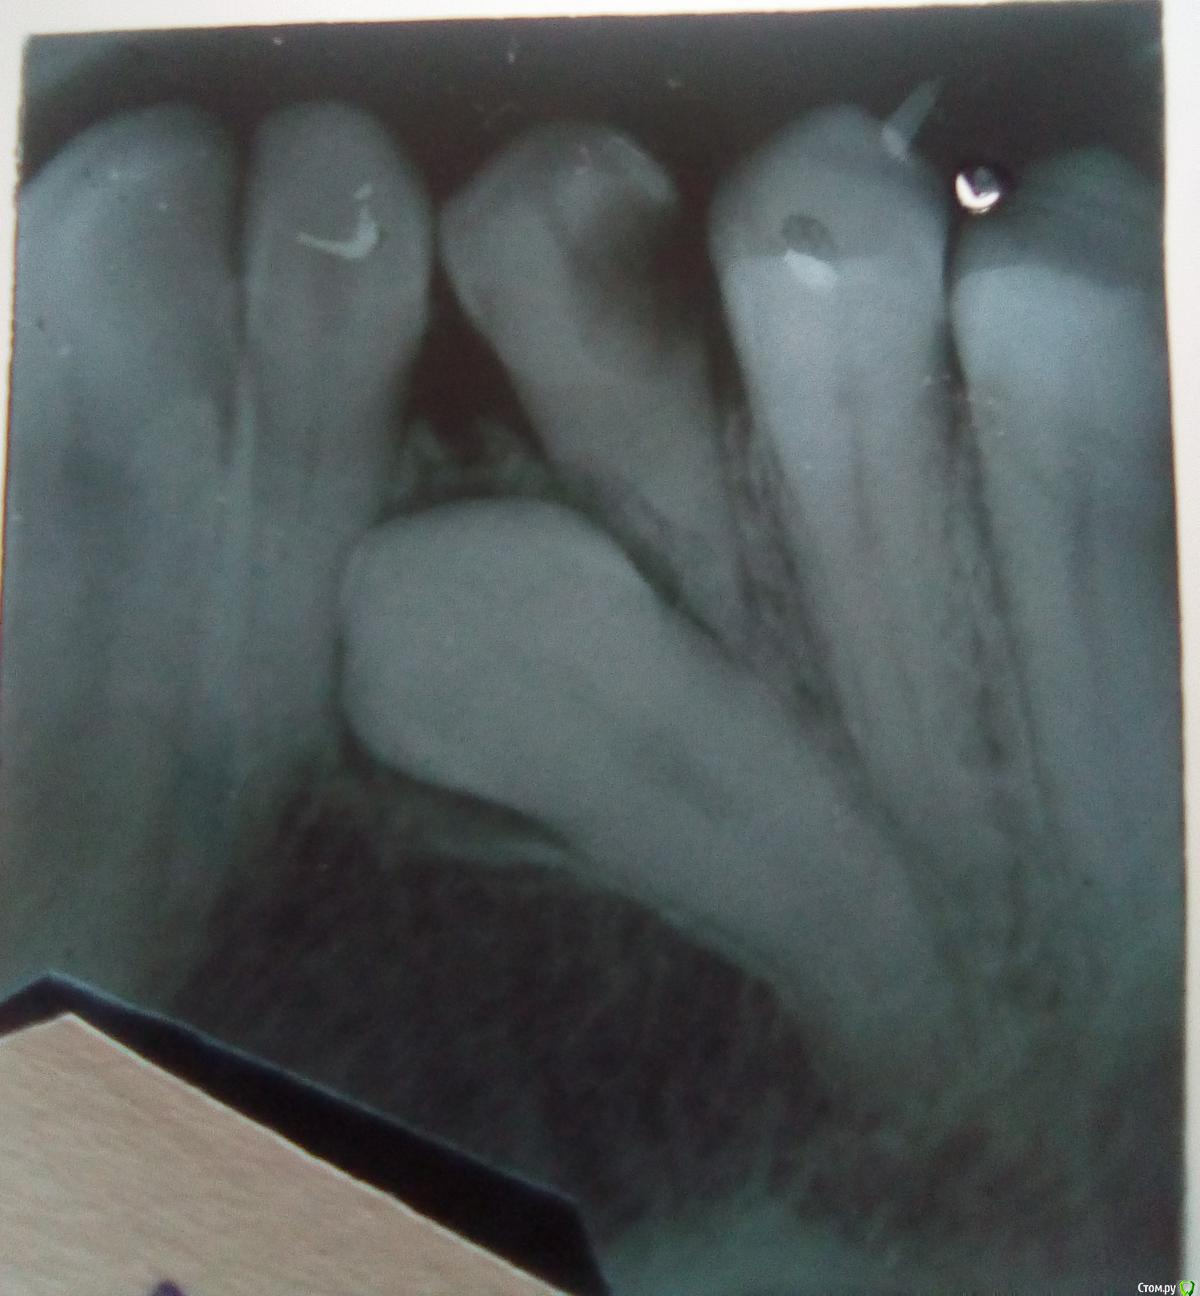

Александр Седаков Опубликовано 17 мая, 2020 Поделиться Опубликовано 17 мая, 2020 Всем здравствуйте! Мне 34 года. Коренной клык пломбировали в 10-11 лет. Рентгеновский снимок до вырывания зуба (клыка). Что-то нужно делать или просто ждать? Ссылка на комментарий

Александр Седаков Опубликовано 17 мая, 2020 Автор Поделиться Опубликовано 17 мая, 2020 (изменено) язычно-угловая ретенция 3-ки верхней челюсти... пальпировал дёсна: 3-ка нижней челюсти слева сильно выступает к языку, а 2-ка там же - к губе 15 мая 2020, а снимок за день доа молочный не помню когда... удаляли Изменено 17 мая, 2020 пользователем Александр Седаков Ссылка на комментарий

red_butler Опубликовано 17 мая, 2020 Поделиться Опубликовано 17 мая, 2020 язычно-угловая ретенция 3-ки верхней челюсти... пальпировал дёсна: 3-ка нижней челюсти слева сильно выступает к языку, а 2-ка там же - к губе а молочный не помню когда... удалялиНа снимке молочный клык... его Вам и удалили, постоянный ретенированный. Требуется консультация ортодонта Ссылка на комментарий